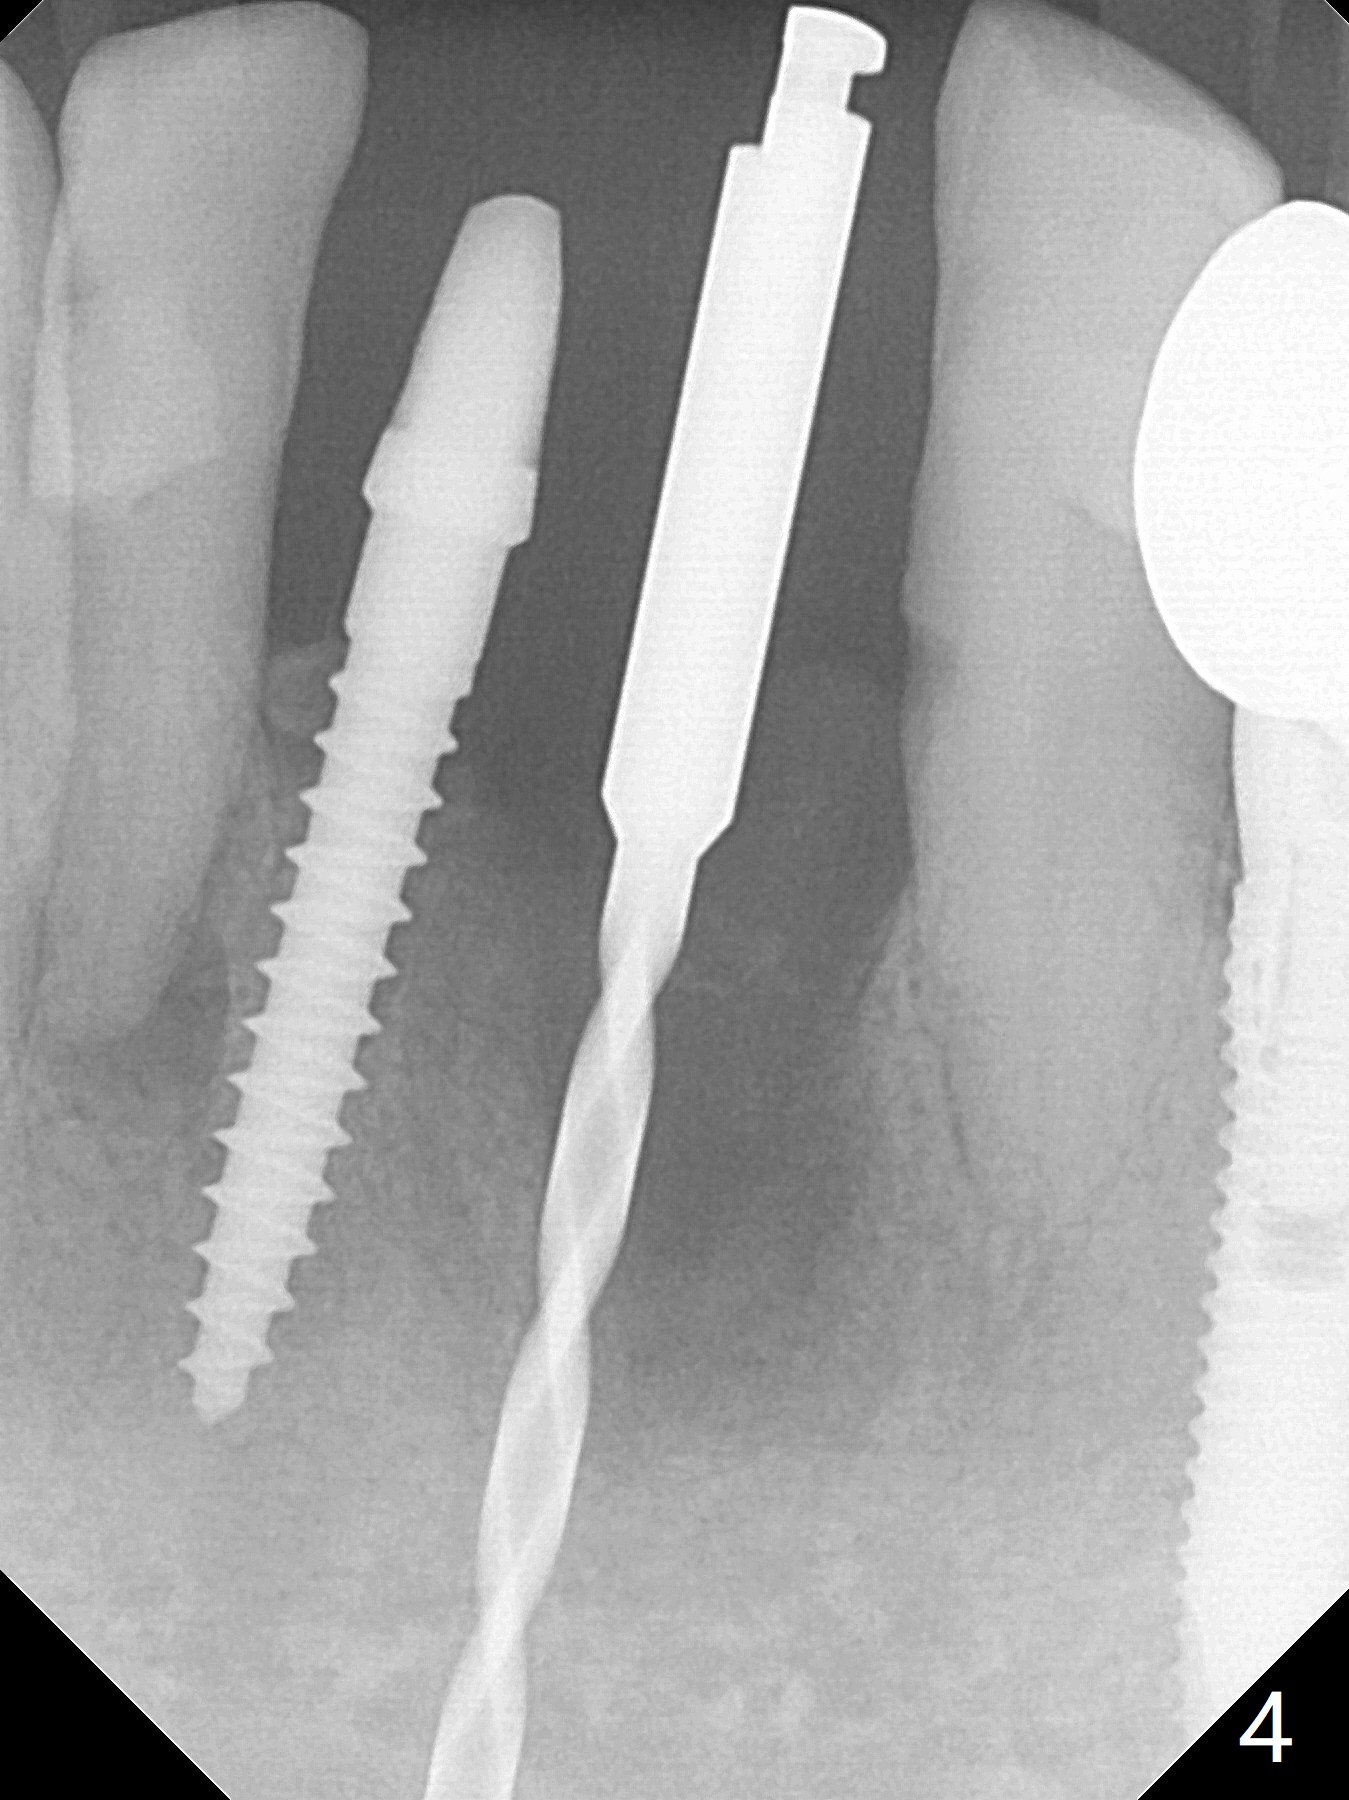

Two and a half months after loss of a 2 mm 1-piece approximately at #23 (Fig.1,2), it appears that the site of #24 (Fig.3 line) is more appropriate because the bone is higher. After removal of the pointed ridge top, osteotomy is initiated with 1.2 mm drill, followed by 1.5 mm one (Fig.4,5). When the 1.5 mm drill is removed, the new osteotomy (Fig.6 *) is mesial to the old one (^). Since the ridge is narrow (Fig.5,6), a 2x14(4) mm 1-piece implant is placed with GBR (Fig.7). Due to overprep, the torque is 20 Ncm. No immediate provisional is fabricated. Instead periodontal dressing is applied around these 2 implants. Two separate provisionals are fabricated when the wound heals. The one at #24 does not stay. The implant at #24 appears to osteointegrate 6.5 months postop (Fig.8). When the crowns are cemented, the margin is supragingival (Fig.9,10). Water Pik is recommended.